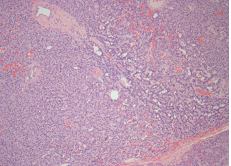

Figure 5a HE 10x: Low –power photomicrograph demostrating a neuroendocrine tumor. The tumor shows solid, ribbonlike, and acinar growth patterns.

Figure 5b HE 40x: Higher magnification showing monomorphous cell, large nuclei and small nucleoli as well as inconspicuous cytoplasma and fine cromatina. Mitoses are rare.